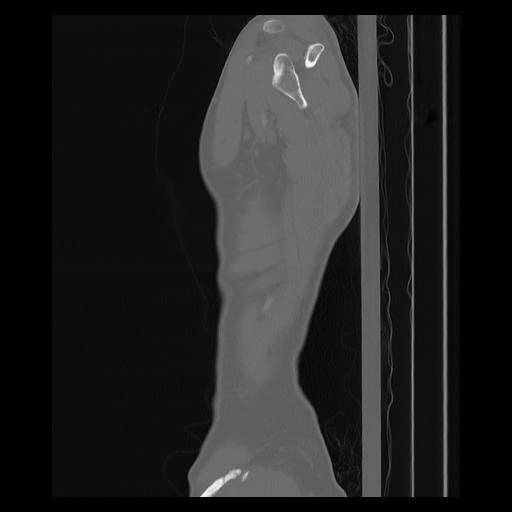

33 PULMON,CE,Sagittal,3.000,PULMON,Sagittal,